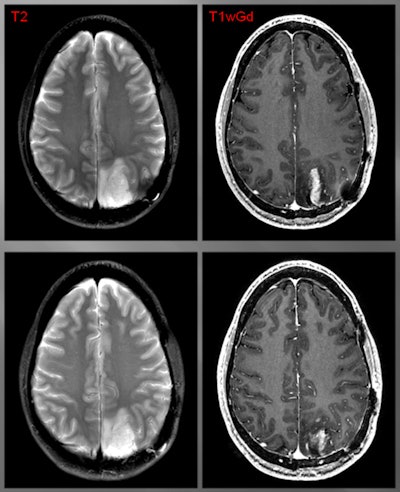

CLR1404-PET successfully imaged tumors with high tumor-to-background uptake and uncovered larger tumor volumes than contrast-enhanced MRI.

"We saw areas of concordant and discordant PET uptake and MRI enhancement," Hall said. "This is what we are really excited about, those discordant areas. Those are the areas where we have the ability to add perhaps more accurate complementary information to what MRI shows."

Patient with a grade III glioma is imaged with T2-weighted MRI (above left). Follow-up gadolinium-enhanced MRI (above right) suggested cancer recurrence. CLR1404-PET detected cancer (below left) and fused PET/MRI (below right) delineated the tumor. All images courtesy of Dr. Lance Hall and UW Health.